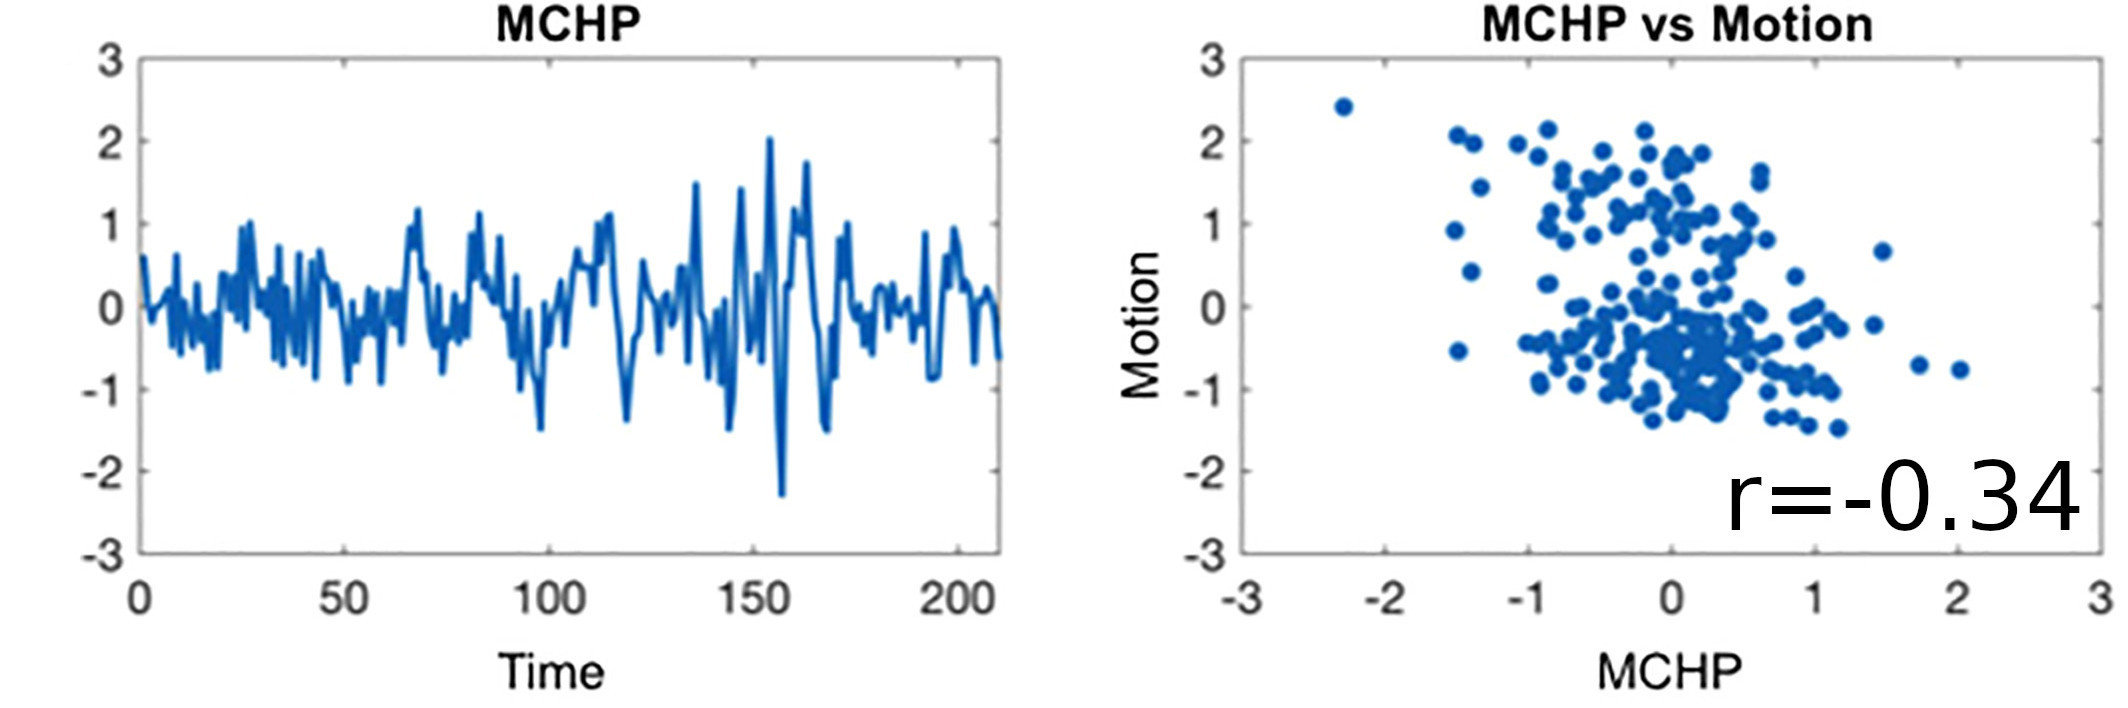

Sequential vs Simultaneous denoising

Performing denoising in sequential steps, rather than in parallel, might reintroduce removed artefacts

Lindquist et al. 2019 (Hum. Brain Mapp.)

Methods: CVR and lag maps

CVR and lag maps: L-GLM with each lagged regressor and nuisance regressors (12 motion parameters and low frequency trends), voxelwise selection of the lagged model with highest explained variance (R²), normalisation to MNI152 template (2.5 mm isotropic)

We compared four pipelines:

- L-GLM with motion parameters (see above, SimMot): $$ Y = P_{ET}CO_2{hrf}_{vx} + Mot + Poly + n $$

- Non-optimised CVR map (measurement delay only, Non Opt): $$ Y = P_{ET}CO_2{hrf}_{bulk} +n $$

- L-GLM without motion parameters (NoMot): $$ Y = P_{ET}CO_2{hrf}_{vx} + n $$

- L-GLM without motion parameters, motion regressed out before (SeqMot): $$ [Y \perp (Mot,Poly)] = P_{ET}CO_2{hrf}_{vx} + n $$

We compared four pipelines:

- L-GLM with motion parameters (see above, SimMot): $$ Y = P_{ET}CO_2{hrf}_{vx} + Mot + Poly + n $$

- Non-optimised CVR map (measurement delay only, Non Opt): $$ Y = P_{ET}CO_2{hrf}_{bulk} +n $$

- L-GLM without motion parameters (NoMot): $$ Y = P_{ET}CO_2{hrf}_{vx} + n $$

- L-GLM without motion parameters, motion regressed out before (SeqMot): $$ [Y \perp (Mot,Poly)] = P_{ET}CO_2{hrf}_{vx} + n $$

Non optimising leads to underestimate the CVR, especially in subcortical areas.

Lag maps show anatomical consistency

Different lag responses, coherent with previous evidence (e.g. Putamen has earlier response than GM)

Area mostly affected by motion! →

Moia, Stickland, et al. 2020 (EMBC)

To improve CVR estimates, compute lagged-regression of signal of interest and noise simultaneously.

Take home message #2